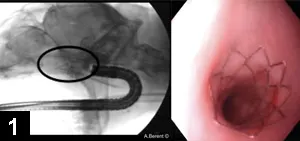

Figure 2. Tracheal polyp in a dog during endoscopic polypectomy

Because tracheal tumors are often located in the intrathoracic trachea, surgical removal via resection and anastomosis can be associated with significant morbidity. However, polypoid masses (eg, tracheal polyp [Figure 2]), extra­medullary plasmacytoma, leiomyoma/leiomyosarcoma) can be effectively resected by using electrocautery snares during biopsy, allowing concurrent diagnosis and treatment. If the mass is broad based and not amenable to polypectomy, a laser (diode or CO<sub2sub>) or stent can help open the airway. Tracheal stents are safe, are highly effective, can be placed quickly, and can be useful in treating nonresectable masses.